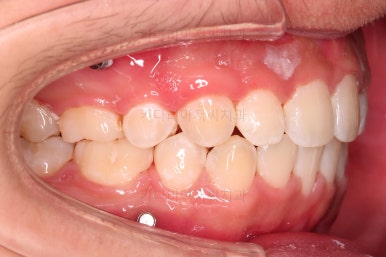

초진 시 입안의 모습입니다.

앞니가 많이 삐뚤고, 송곳니가 부각되어 덧니처럼 보이네요.